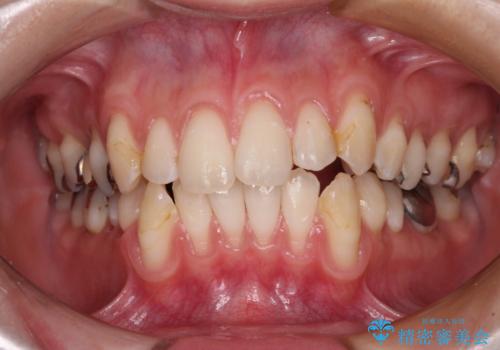

- 歯肉退縮による知覚過敏を気にして来院された患者様です。

診察したところ、知覚過敏をむし歯と勘違いし、一生懸命磨いたことで横縞模様ができるほどでした。

歯肉退縮に対して、上顎からの結合組織移植術(CTG)により、歯根の被覆を行うとともに、歯肉の厚みを増すことで将来の退縮リスクを抑制することとしました。